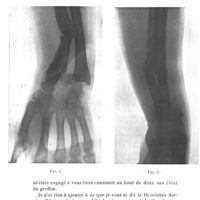

0209 - Page 203 - Séance du 29 janvier 1913. Présentations de malades. Greffe adipeuse. Résultat éloigné d'un vaste évidement du tibia traité avec succès par la greffe adipeuse en 1904. Radiographie, M. Chaput0209 - Page 203 - Séance du 29 janvier 1913. Présentations de malades. Greffe adipeuse. Résultat éloigné d'un vaste évidement du tibia traité avec succès par la greffe adipeuse en 1904. Radiographie, M. Chaput